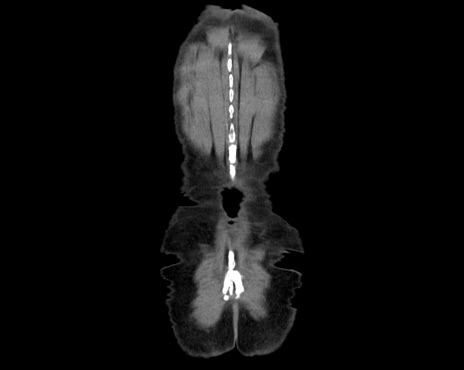

症例26(冠状断像)

横断像